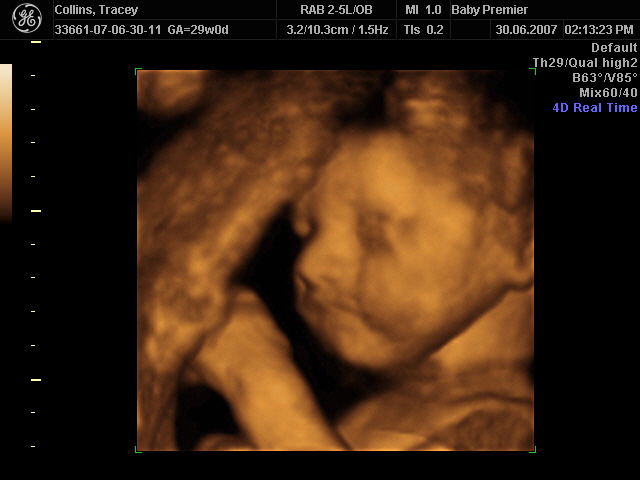

On 30th June 2007, we had a scan of our baby done in "4D" - fancy speak for a moving 3D image.

So sit back, relax, and enjoy Baby O in glorious 4D!